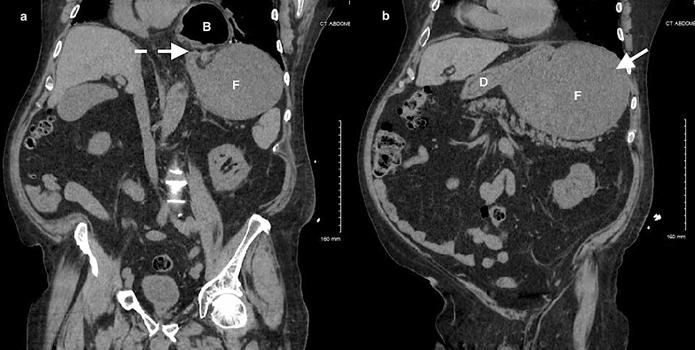

加急CT检查显示中至大型食管裂孔疝和由于胃扭转而呈现的胃部水肿膨胀并伴有部分梗阻(图3-5)。

(图3)

(图4)

当怀疑有胃扭转时,选择初始的影像学检查非常重要,因为诊断延迟可能导致致命的并发症。CT检查高度可靠,主要有两种表现,即正常的胃窦幽门移行区和胃窦位置异常,诊断急性胃扭转的敏感性和特异性均为100%。POCUS是一种有效的非侵入性影像检查方式,主要用于床旁评估。此外,POCUS无辐射,并可根据临床情况随时进行重复检查。本例患者POCUS检查显示,胃部严重扩张,胃内容物分层,类似胃出口梗阻(GOO)的“黑白饼干”征象。POCUS还可以用来动态观察胃减压成功与否。